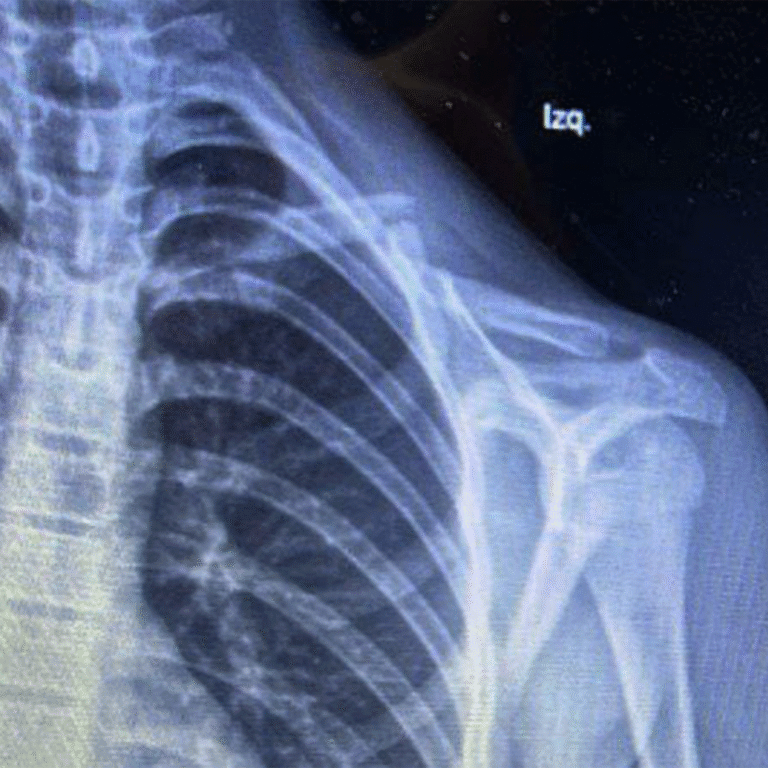

🩺 Resultados que transforman vidas. Descubre cómo hemos devuelto la movilidad y eliminado el dolor de mis pacientes mediante tratamientos efectivos.